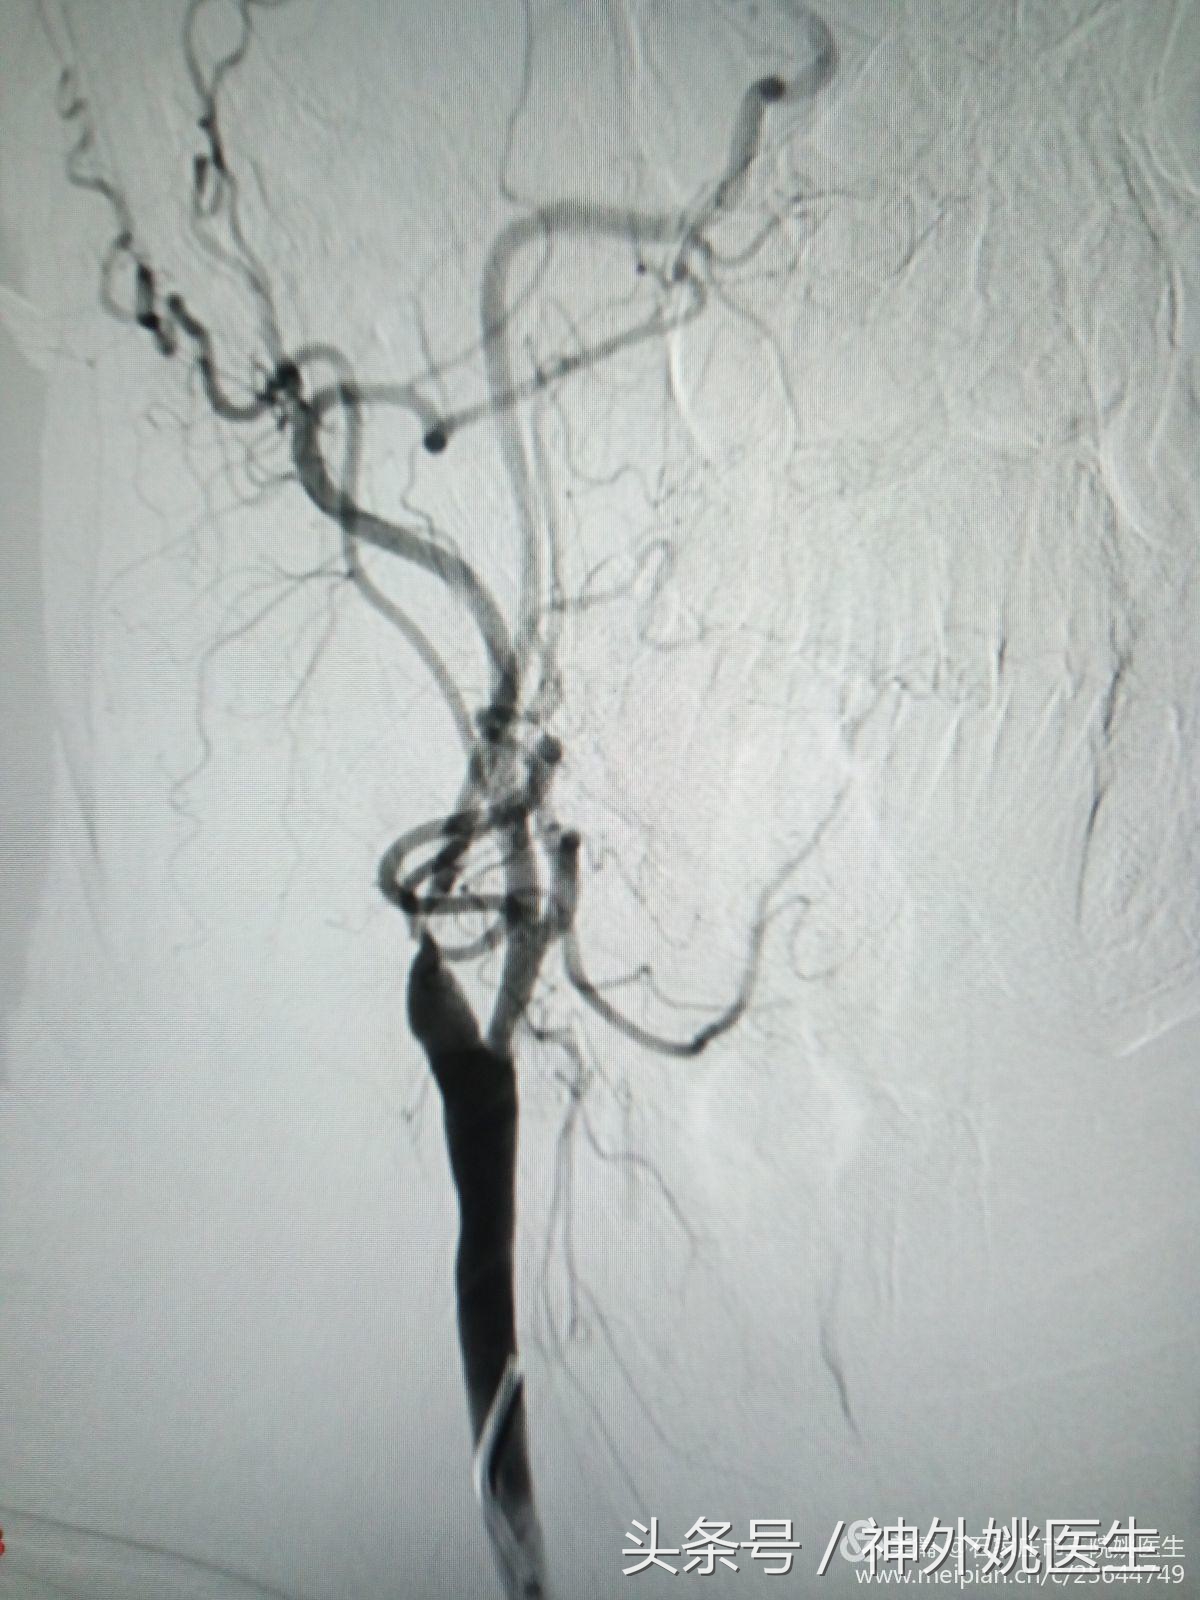

术前评估(DSA):

1.右颈动脉造影示:右颈内动脉狭窄部位位于球部以远,狭窄远端管腔明显变细(图6、图7)。狭窄段远端平下颌角及C2/3椎间盘水平(图8)。提示位置较高,操作难度较大。缝合时需精细操作,避免管径丢失,术后管腔狭窄。

图6

图7

(图8)